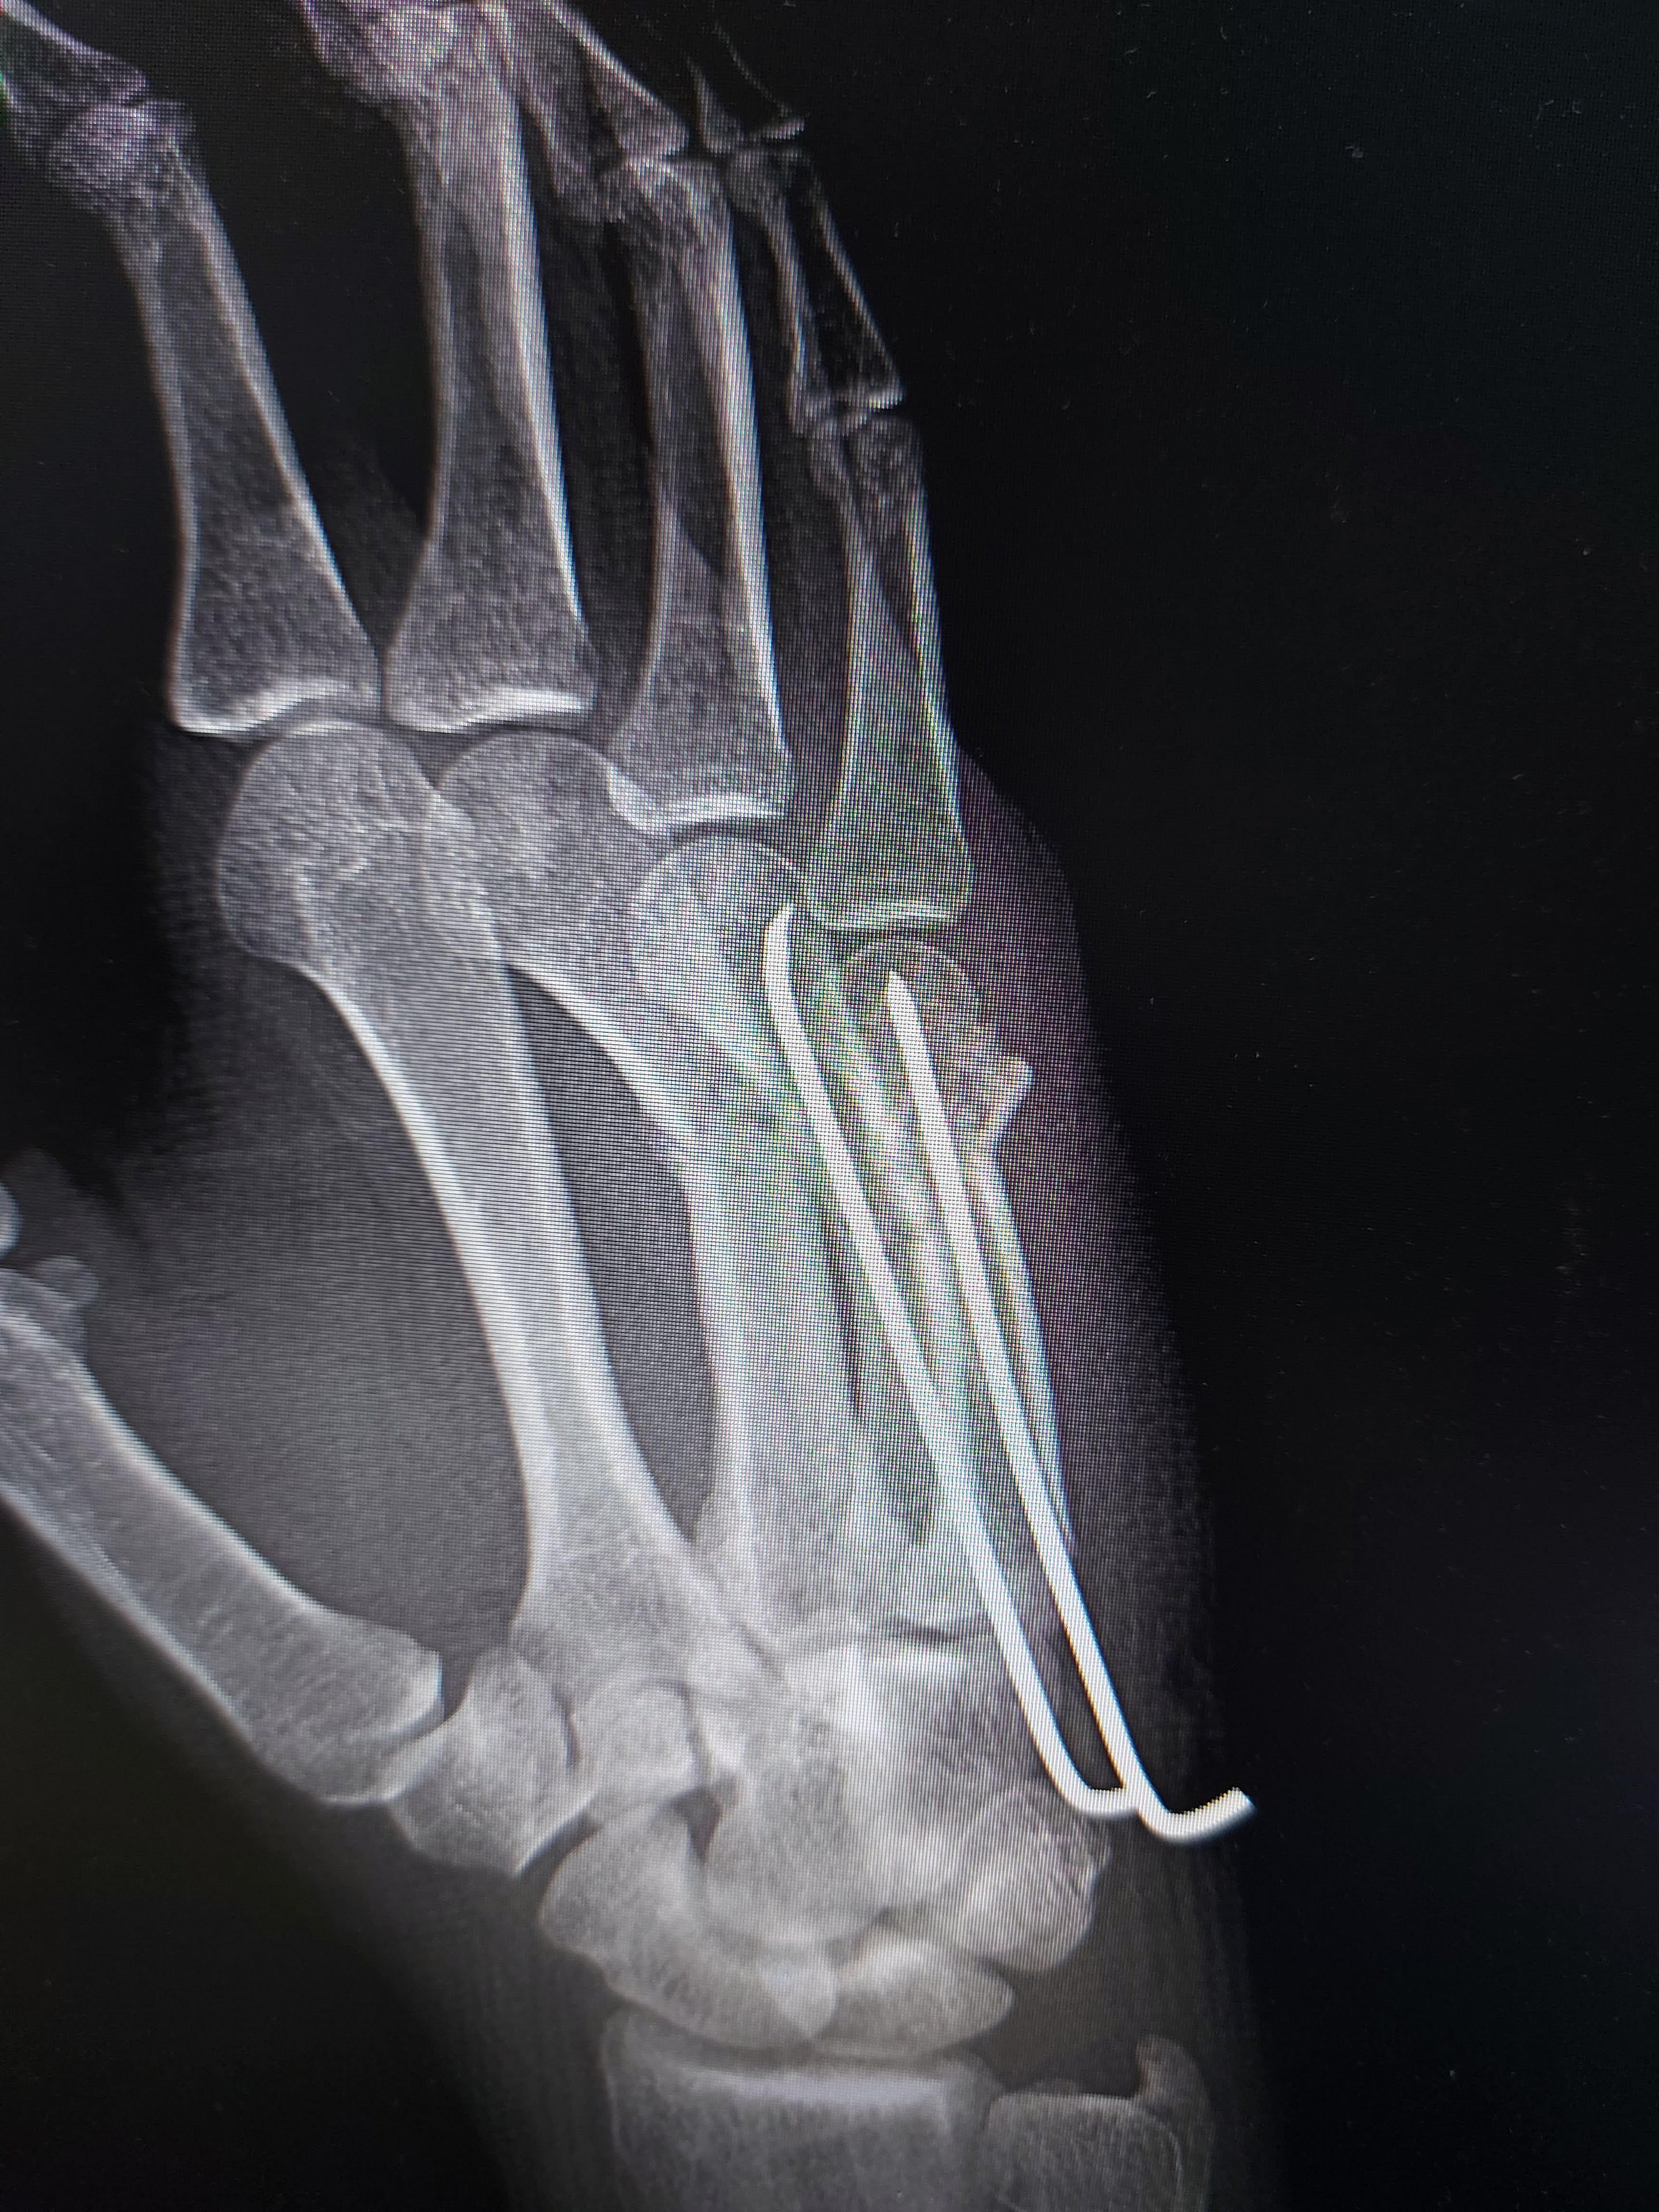

Fractura metacarpiene III, IV, V